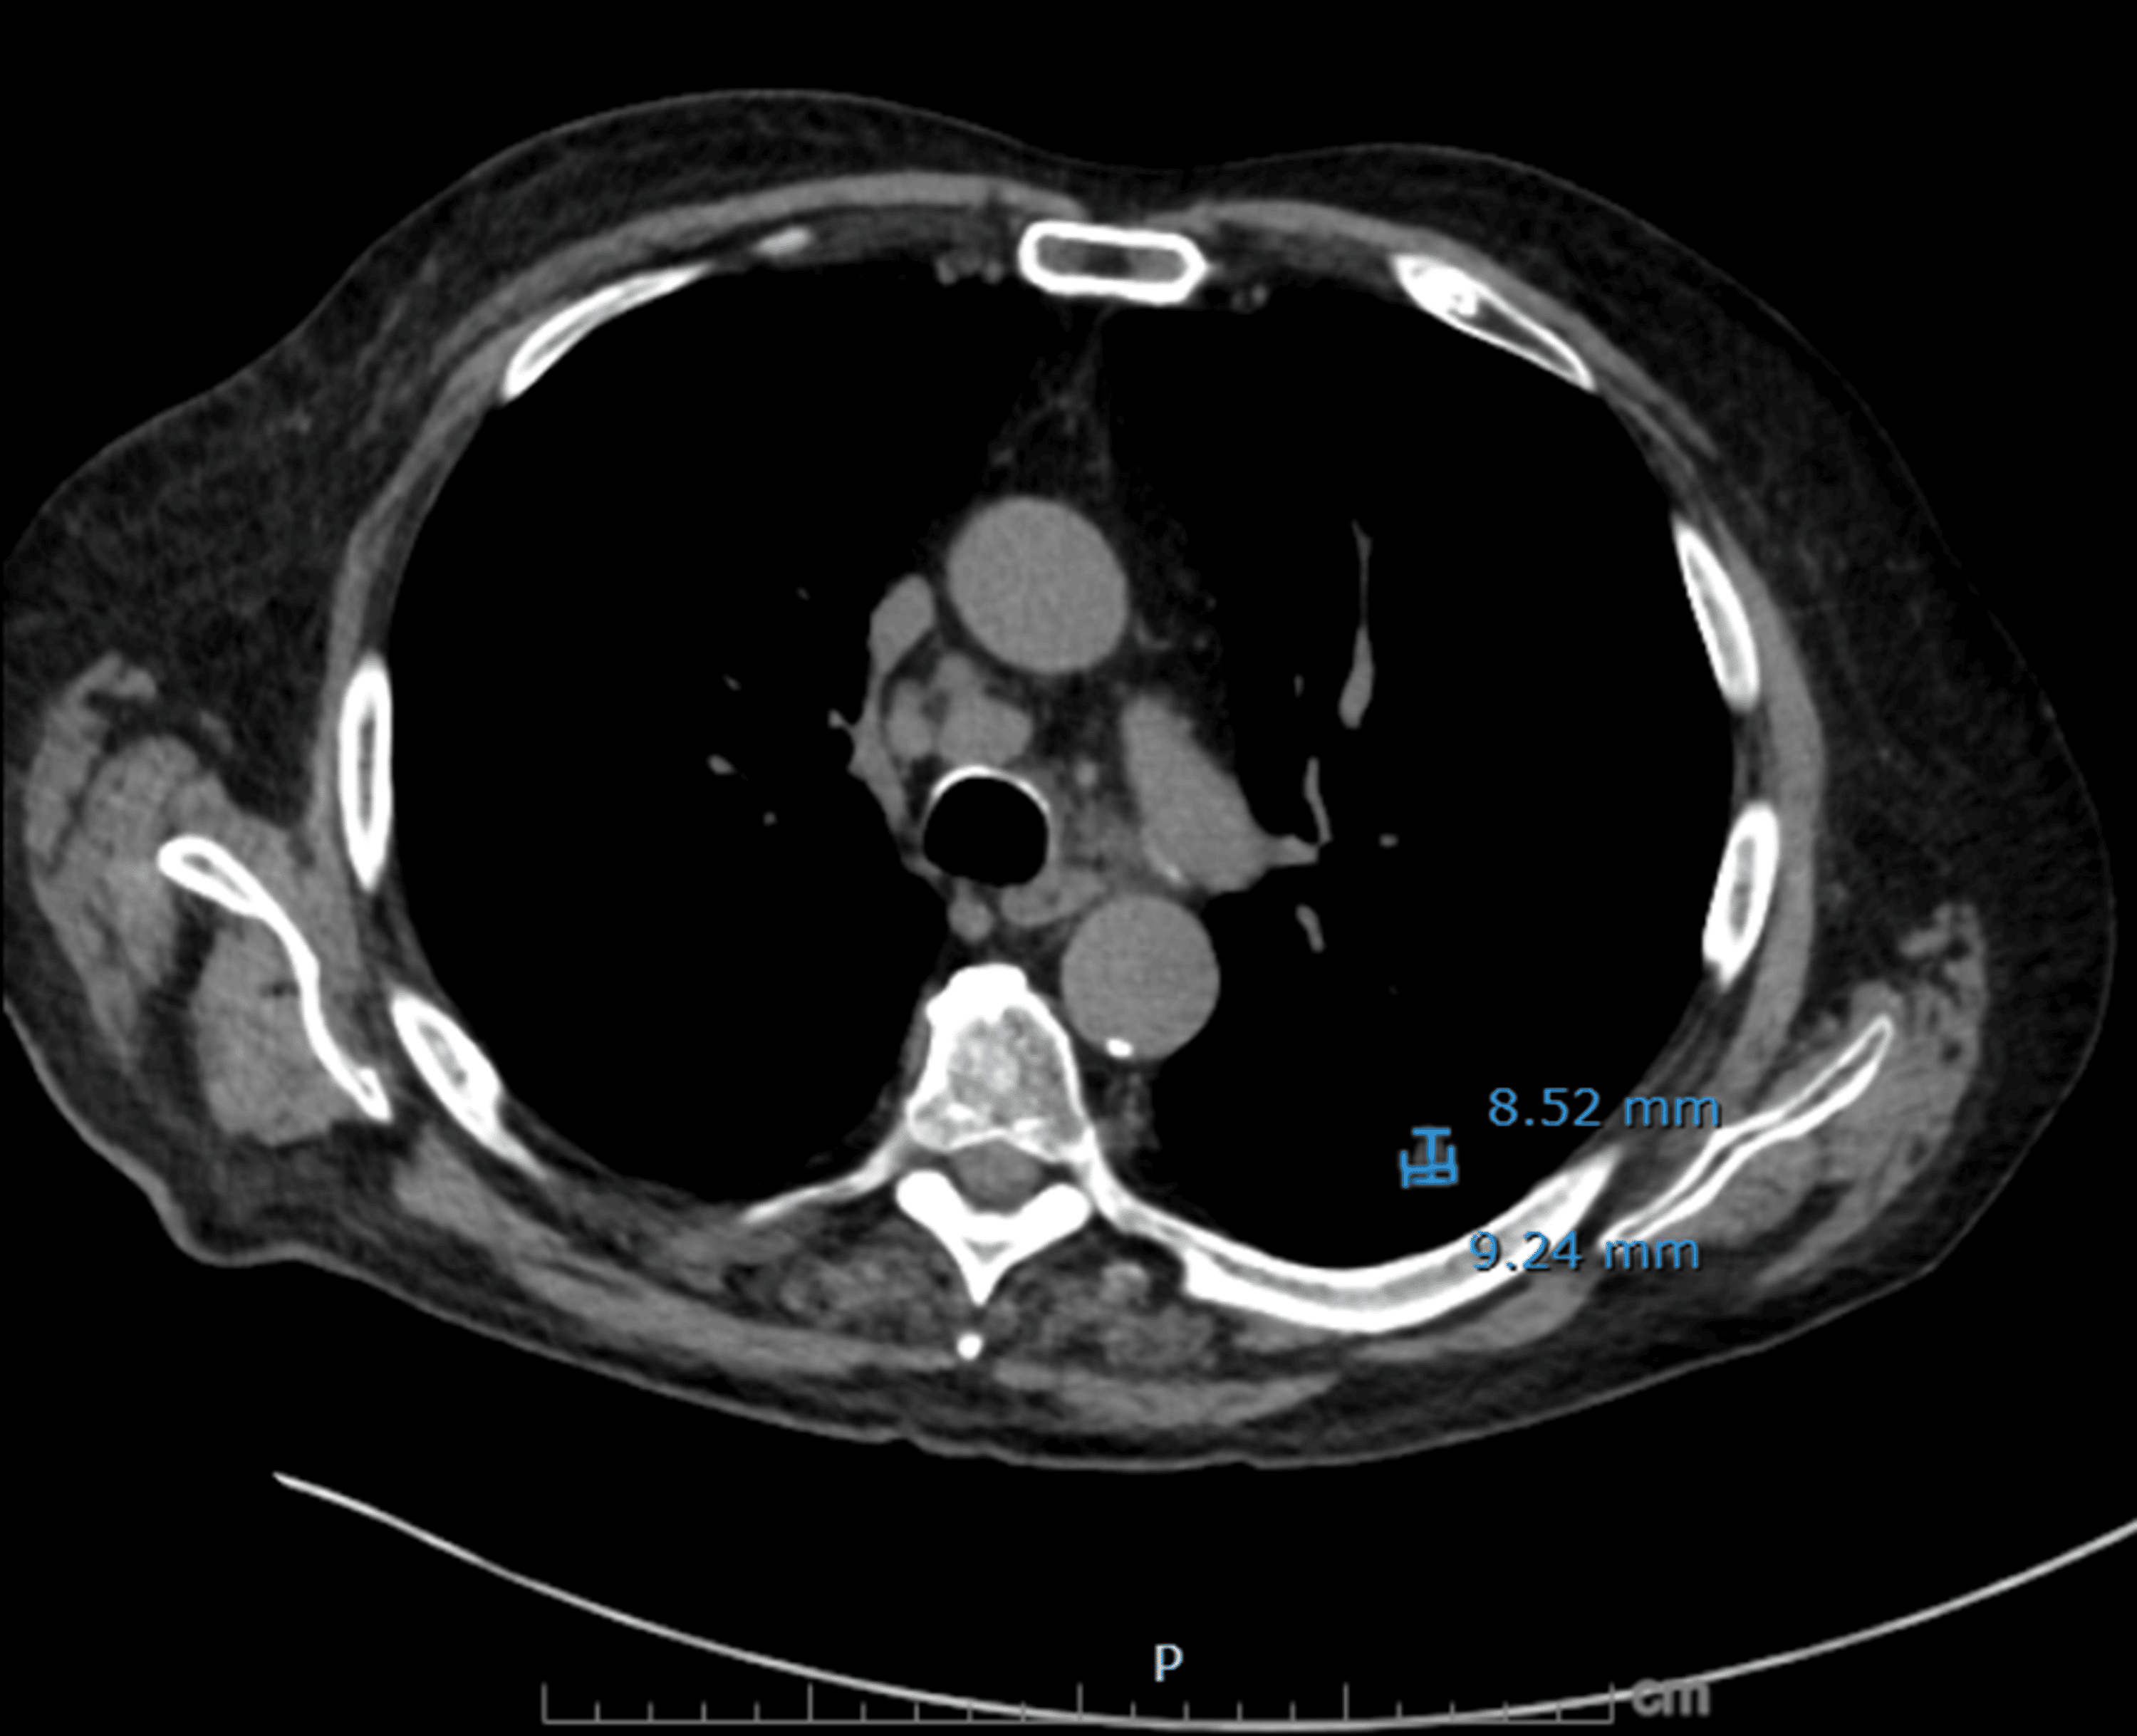

Figure 3: Axial non-contrast CT chest demonstrating residual treated left lower lobe lesion

A spiculated nodule in the left lower lobe measuring 9.2 mm (AP) × 8.5 mm (transverse) on image 60, slightly decreased from the prior measurement of 9.3 × 10.6 mm, corresponding to the site of previously treated squamous cell carcinoma.